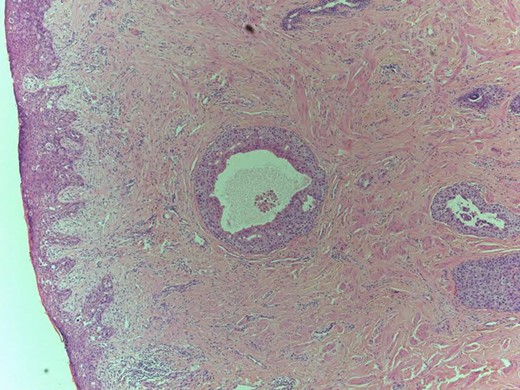

Histology: consistent with non-invasive Paget's disease of the nipplè (Fig. 1), associated with 11 mm focus of underlying high-grade DCIS of solid and micropapillary type (Fig. 2). There was no invasive disease. Sentinel node biopsy was clear.